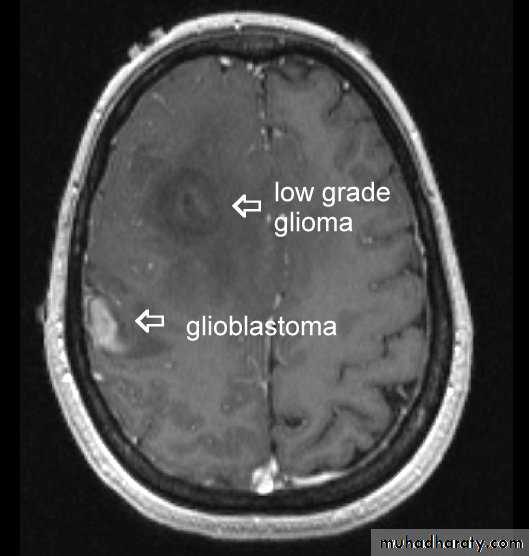

Astrocytomas:have 4 grades I -> IV. These are the most common gliomas, there are 4 grade of astrocytoma depending on the degree of malignancy, it can affect any age , usually yellow - whitish in color affecting both cerebrum and cerebellum , it can affect ages from 2 months ~ 95 years.

Glioblastoma multiformis:

The most malignant brain tumor, rapidly growing , red in color, highly vascular mainly affecting the cerebrum , some pathologists classify it as astrocytoma grade IV.Medulloblastoma:

arise from the epidermal lining of the ventricular system, usually whitish in color & can lead to early hydrocephalusCT scan of all gliomas shows usually hyperdense lesion, irregular in shape, surrounded by edema & may be enhanced with or without cystic degeneration.

Note: all gliomas are dealt with by surgical intervention ,by excision of the tumor followed by radiotherapy , but prognosis is not very good & fluctuates from 5 years survival of less than 5% in Glioblastoma multiformis to up to 100% 5 years survival in Oligodendroglioma treated by surgery & successive radiotherapy.